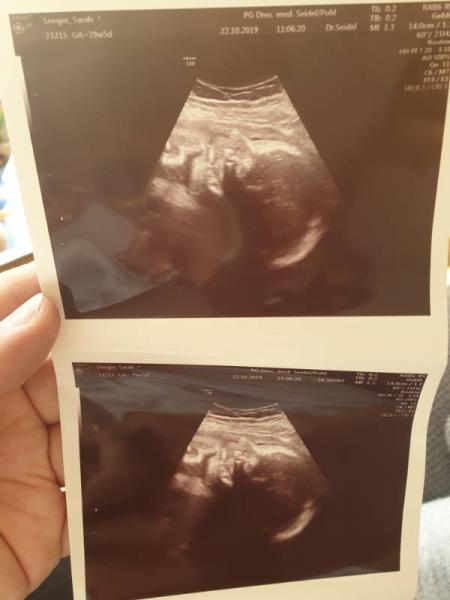

Sooo heute war wieder unsere 3 große Untersuchung. Und zusätzlich CTG, ja was soll ich sagen, also unsere Maus mag das ja mal so garnicht Ständig rutschte sie weg, dann kam die Schwester rein und hatte es nochmal versucht und dann klappte es mal nach einer Weile. Am Ende hat die Maus so doll gestrampelt und geboxt das es richtig laut war. Schwestern sagte auch der kleinen scheint es nicht so zugefallen. Aber ich empfand es Wunderschön. Danach ging es zur Ärztin ins Ultraschall und da war auch alles perfekt. Die Motte wiegt jetzt 1440 Gramm und wollte und natürlich mal wieder kein Gesicht zeigen bissel schüchtern. Meine Ärztin meinte dann auch ich bekomme ein Beschäftigungsverbot, ich habe lange genug durchgehalten. Ich hatte dann bissel geschaut wie nen Reh und fragte ob ich wenigstens noch heute meine Spät machen darf. Aber die war eisern und sagte Danach bin ich erstmal zur Arbeit und hatte alles angegeben, jetzt muss leider meine Lieblingskollegin einspringen im ihrem frei. Hab voll das schlechte gewissen, aber alle meinten ich habe für einen Einzelhandel sehr lange durchgehalten und soll mich jetzt entspannen und meine Restschwangerschaft genießen. Na gut hab mir jetzt 4 neue Bücher für 75 Euro gekauft

Bild zu Arzttermin - Forum für Januar - Mamis